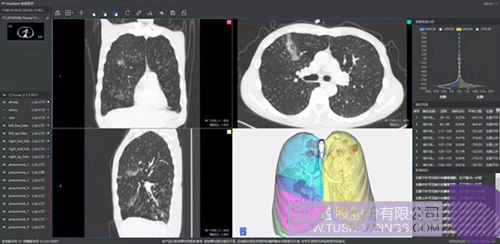

柏視醫療

640-3.jpeg

推出的新冠肺炎輔助篩查系統借助AI技術可行之有效地輔助大規模新冠肺炎病例的影像篩查工作。同時基于肺部結構快速智能分割,讓醫生對肺部病變情況一目了然。還可結合臨床征象,自動生成符合最新型冠狀病毒指南的結構化圖文報告,輔助醫生大幅提升診斷效率,同時提高診斷準確性。